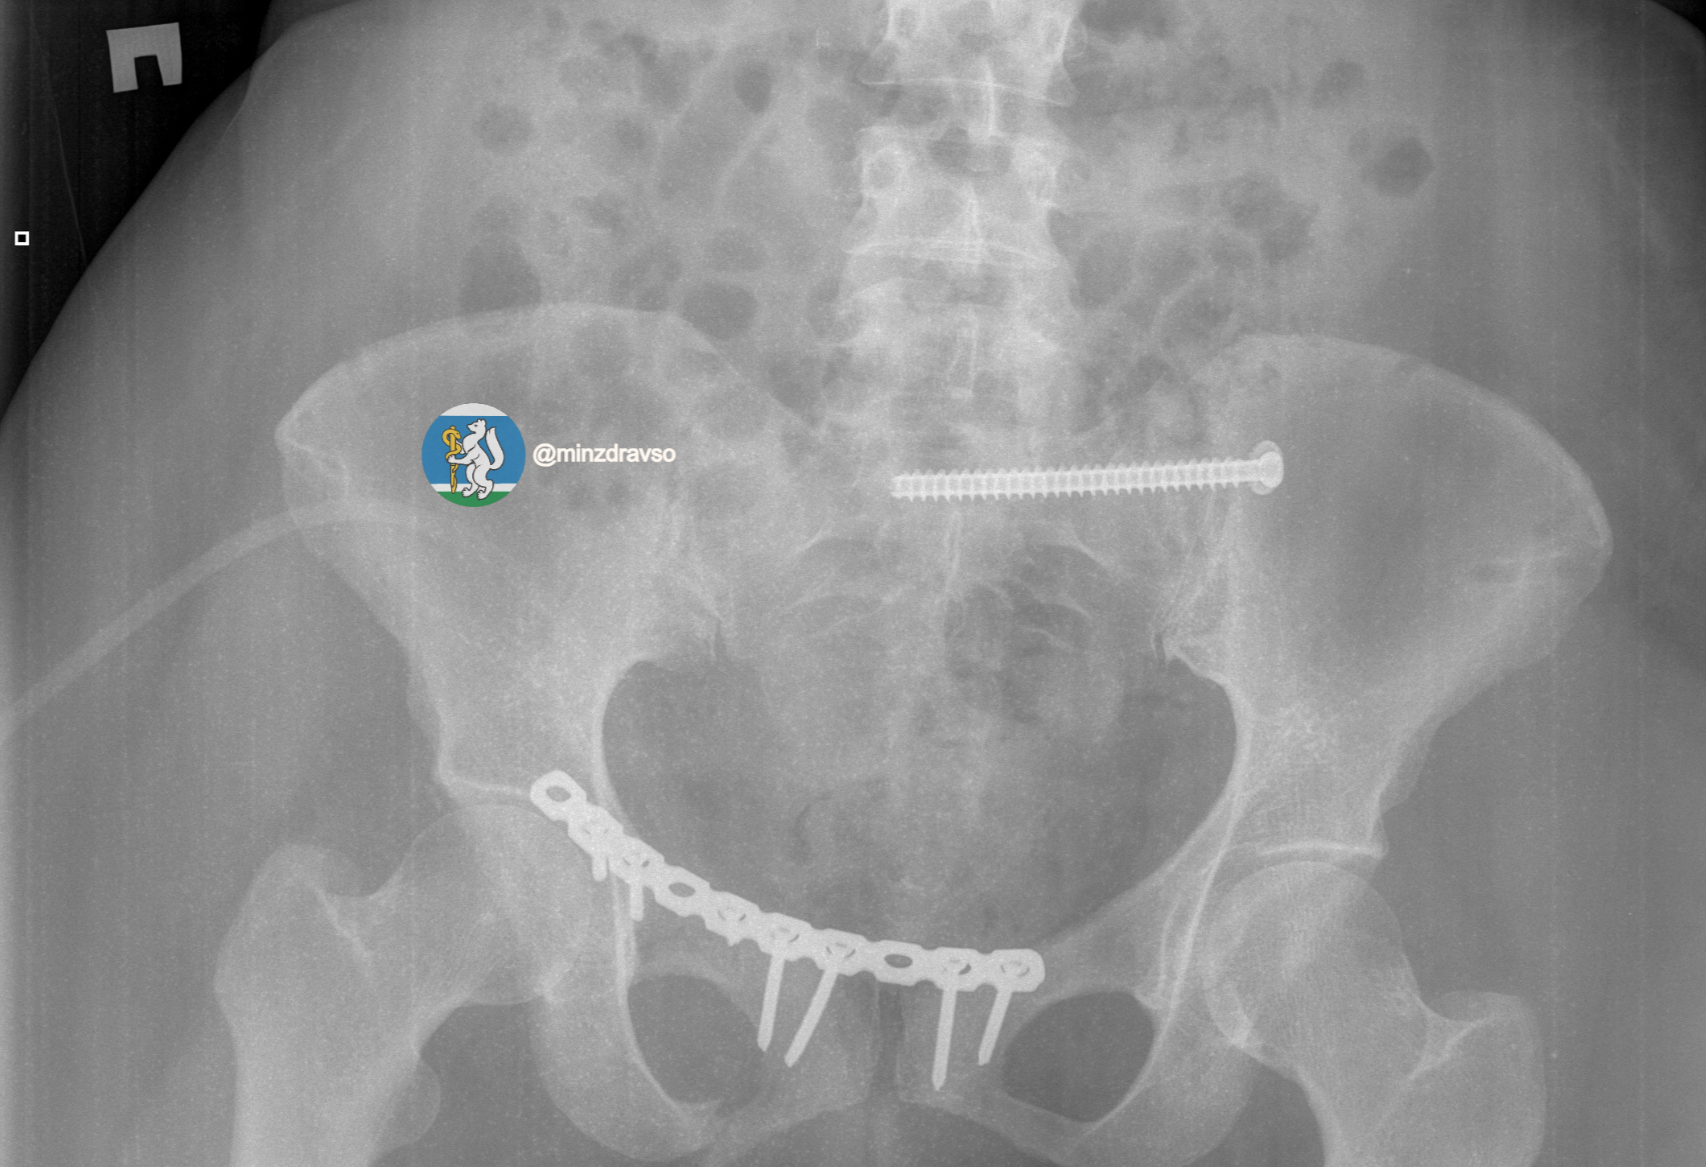

Профессионализм и опыт врачей, их высочайшая квалификация и плановое совершенствование экстренной медицинской помощи в Свердловской области позволили пациентке получить второй день рождения. Тактика врачей позволила купировать шоковое состояние и подготовить организм к основному хирургическому этапу. Череду вмешательств завершил демонтаж аппаратов внешней фиксации таза и установка внутренних металлофиксаторов на ключицу и кости таза.

Врачам удалось дважды совершить практически невозможное: они не только спасли жертву ДТП с тяжелейшими повреждениями, но и минимизировали последствия травм, сохранив женщине качество жизни. Через месяц после страшной аварии она смогла вернуться домой. Благодаря реализации в регионе нацпроекта «Продолжительная и активная жизнь» врачи смогли превратить сложный клинический случай в историю успешного выздоровления.